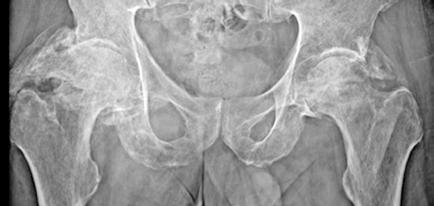

Se solicita una Ecografía abdominal donde se visualiza una masa hepática de aproximadamente 12 cm y directamente se solicita una Tomografía Computarizada (TC) urgente. Se confirma la masa hepática, que mide 13x11x10 cm, con signos de sangrado reciente pero sin sangrado activo.

Localizada en los segmentos VII, V y parte del IV, entre las venas suprahepáticas (VSH) derecha y media, contactando con ellas en su origen. Caudalmente llega hasta la bifurcación hiliar, cercano a la bifurcación portal. Esta masa presenta una captación periférica en fase arterial y algo más isodensa en fase venosa y tardía, con un área central heterogénea e hipodensa en estas últimas fases. Con este comportamiento radiológico, se establece un diagnóstico de sospecha de hepatocarcinoma fibrolamelar o adenoma. Como variante anatómica, se objetiva una arteria hepática que nace de la arteria mesentérica superior (Figura 1). El paciente es ingresado en Digestivo para estudiar la lesión. Se realiza una Resonancia Magnética (RM) y se establece un diagnóstico de sospecha de hepatocarcinoma fibrolamelar (Figura 2). Se descartó una biopsia por el riesgo de resangrado que presentaba. La alfafeto proteína solicitada durante el ingreso fue normal. Dado que se trata de una lesión hepática sintomática y que ha presentado un sangrado, está indicada la resección de la lesión, pero su tamaño y localización lo impiden. La lesión está tan cerca de las VSH que resulta imposible disecarlas y seccionarlas con seguridad, siendo imposible la cirugía. Se comenta el caso en el comité multidisciplinar y se decide embolizar la tumoración con el objetivo de evitar un nuevo sangrado y disminuir su tamaño para separarla de las estructuras vasculares. Se cateteriza la arteria hepática, desde la mesentérica superior. Se emboliza con micropartículas

la hepática derecha y una rama más distal de la hepática izquierda, preservándose los segmentos II y III. (Figura 3)

En el TC de control la lesión ha disminuido de tamaño a 10 x 7.4cm. Se realiza además una volumetría hepática y los segmentos I-III suponen el 29 % de la masa hepática, siendo este remanente insuficiente. Con la embolización, la lesión se ha reducido de tamaño pero sigue contactando con el nacimiento de las VSH media y derecha. Su resección exige realizar una hepatectomia derecha ampliada. Precisa pasar y ligar ambas venas en su origen y sigue siendo el acceso complejo por tener delante la masa. Se sigue considerando de dudosa resecabilidad por el difícil acceso a las VSH y el riesgo hemorrágico. Se decide realizar una nueva embolización para reducir aún más el tamaño tumoral, esta vez con radioesferas de Y90. Esta segunda embolización es más selectiva y con poca afectación del parénquima sano.

Tres meses después se realiza un nuevo TC de control, que muestra la lesión en el mismo lugar, actualmente de 7,4x5,9 cm de diámetros (previo de 9,8x7,5 cm). En la actualidad se ha alejado de las VSH, pero contacta y desplaza la vena porta derecha y la arteria hepática. Además se visualiza una leve dilatación de la vía biliar intrahepática izquierda, de nueva aparición. Se presenta en comité una vez más y se decide colocar un drenaje biliar interno-externo, dado la dilatación de vía biliar que presenta el paciente. Además se realiza una embolización portal derecha, para así aumentar el remanente del hígado izquierdo que era del 29%. Se realiza una nueva volumetría hepática tras la embolización portal y se comprueba que el futuro remanente hepático había aumentado al 42%.

Resumiendo: Teníamos una masa hepática inicialmente irresecable que se ha tratado con dos embolizaciones arteriales, consiguiendo una disminución del tamaño y una mayor separación de las venas suprahepáticas. Sin embargo, se ha acercado a la bifurcación portal y comprime la vía biliar (dilata la vía intrahepática izquierda asociando una elevación de bilirrubina). Se ha colocado un drenaje biliar interno-externo. Se ha embolizado la porta derecha, consiguiendo pasar de un volumen de remante hepático del 29% al 42%, siendo ahora posible su resección. El acceso a las VSH sigue siendo complejo y arriesgado, pero menos que al inicio (Figura 4).